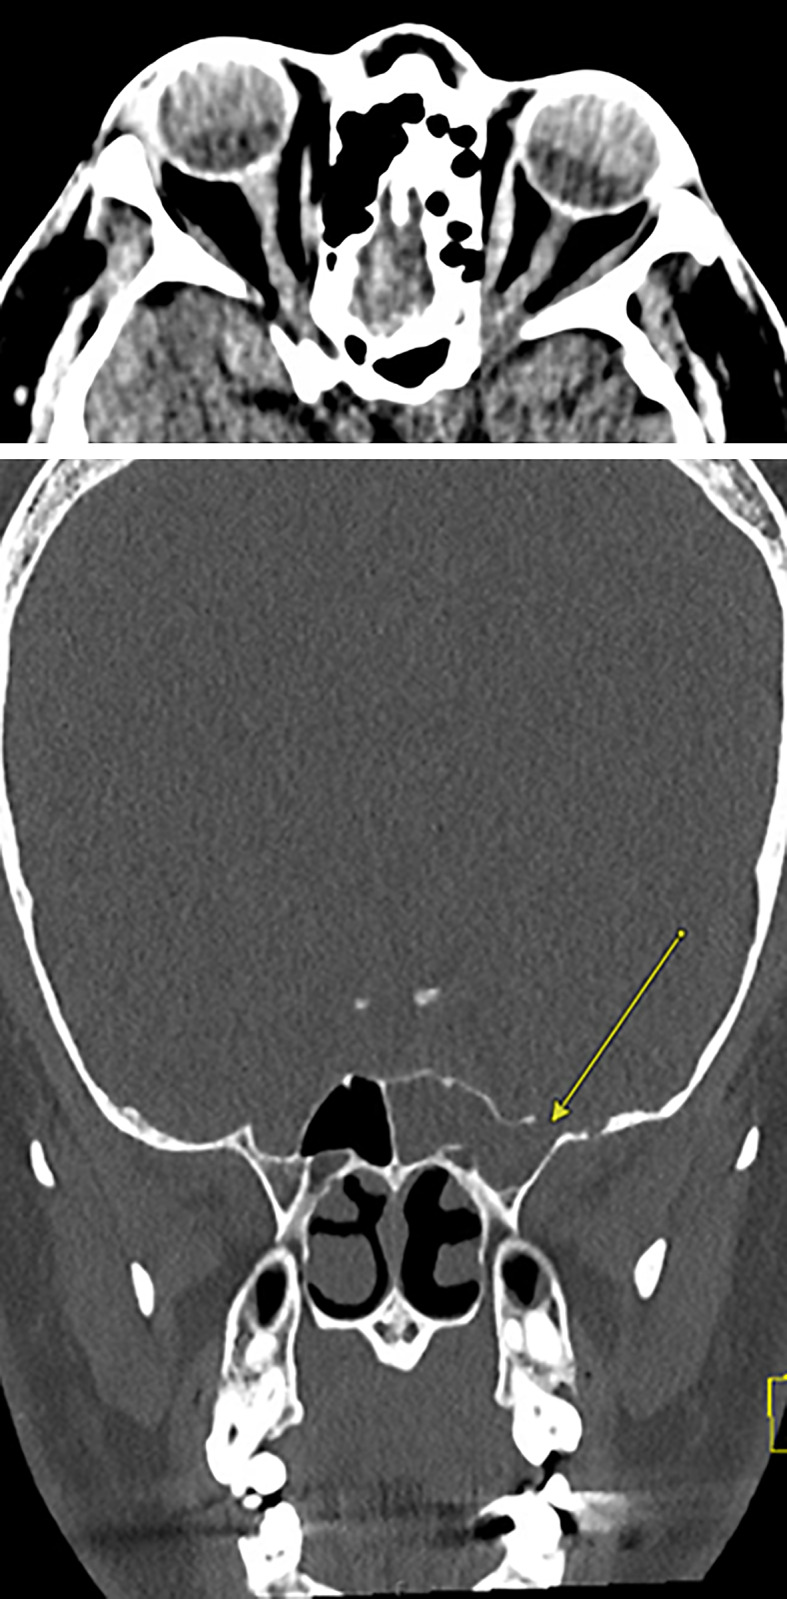

简介特发性颅内高压(IIH)的病理生理学尚未完全定性,而变性患者的发病情况也鲜为人知。变性患者的特发性颅内高压病例已有数例报道,但将脑脊液(CSF)漏视为变性患者特发性颅内高压并发症的病例却较少。这些患者可以作为一个重要的研究人群,因为核型女性使用外源性睾酮与 IIH 的发生之间的关联可能支持这种疾病由激素介导的发病机制:我们描述了一例 33 岁的肥胖(体重指数:30.58 kg/m2)女变男患者的病例,该患者使用外源性睾酮已有 15 年之久。眼底镜检查发现眼盘苍白和水肿,符合弗里森 3 级乳头水肿。鼻腔分泌物中的β-2转铁蛋白呈阳性,与脑脊液一致。头部计算机断层扫描显示,左侧中颅窝内侧有一个 5 毫米的缺损,双侧视神经突出和迂曲,蛛网膜颗粒异常,与 IIH 有关。在内窥镜下成功修复左侧蝶骨外侧凹漏后,患者仍报告头痛,开始服用乙酰唑胺,症状有所改善:本文描述的病例进一步证实了越来越多的证据表明,激素作用机制与 IIH 的发病有关。重要的是,该病例还说明,有必要加强对变性患者罕见神经系统疾病的研究和交流。

Case presentation: We describe the case of a 33-year-old obese (BMI: 30.58 kg/m2) female-to-male transgender patient on exogenous testosterone for 15 years who presented with 1 month of acute or chronic headache with profuse rhinorrhea. Fundoscopic exam revealed disk pallor and edema consistent with a Frisen grade 3 papilledema. Nasal secretion was positive for beta-2 transferrin, consistent with CSF. Computed tomography head demonstrated a 5-mm defect in the medial left middle cranial fossa, bilateral optic nerve prominence and tortuosity, and abnormal arachnoid granulations concerning for IIH. After a successful endoscopic endonasal repair of the left lateral sphenoid recess leak, our patient continued to report headaches, was started on acetazolamide, and noted improvement in symptoms.